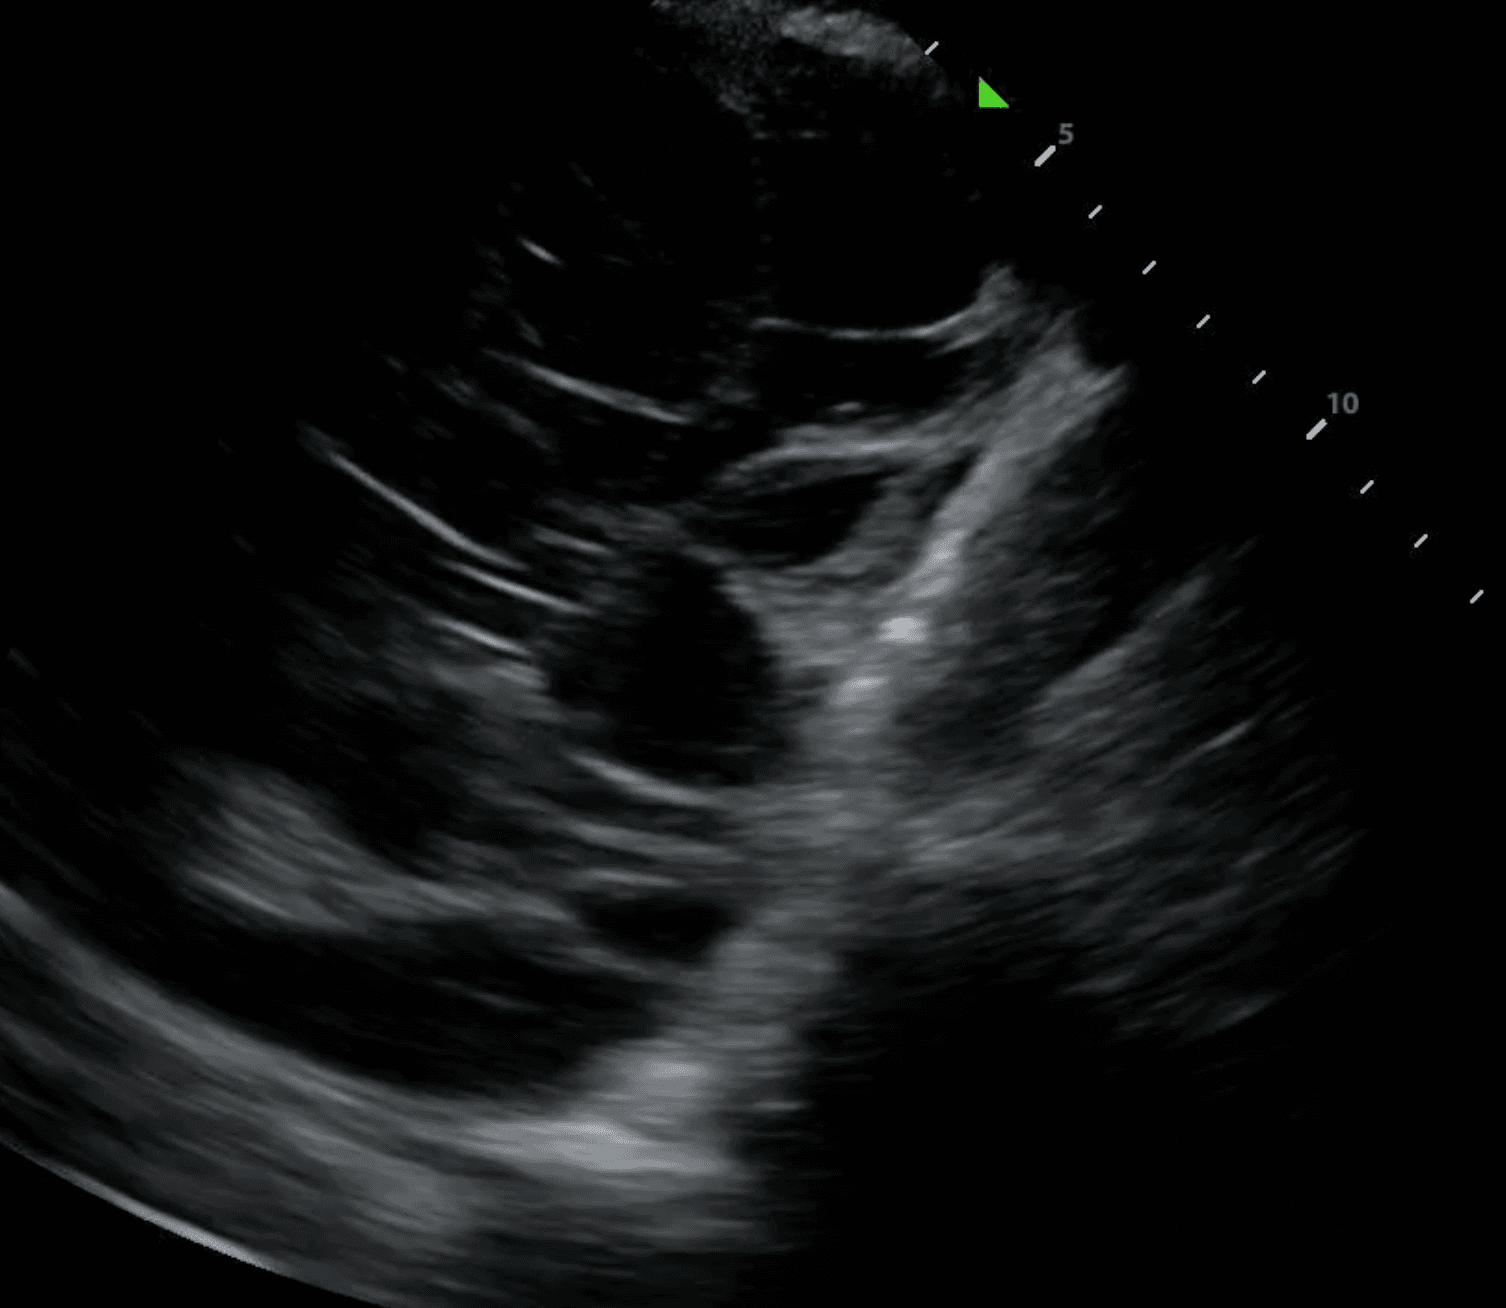

Pleural space pathologies comprise any disease affecting the thin, fluid-fill area between the visceral and parietal pleura. These conditions typically involve the excess accumulation of air (pneumothorax), fluid (ie. pleural effusion), blood (hemothorax) or pus (empyema), expanding the space between the pleural layers. This impedes normal lung function and can lead to significant respiratory distress if left untreated.

Lung ultrasound can be invaluable in determining the appropriate management strategy by differentiating these pathologies. For instance, pneumothorax presents with a distinct pattern of absent lung sliding coupled with A lines due to the scattering of sound waves in air (read more here).

In contrast, pleural effusion, hemothorax and empyema may all present with thickening of the pleural line, but can usually be differentiated based on the presence of anechoic fluid, bright echogenic material or septations (read more here). With lung ultrasound, physicians can diagnose and initiate treatment such as chest tube insertion or antibiotics without leaving the bedside.